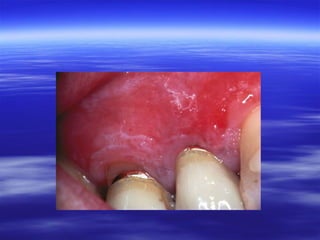

:Chronic Hyperplastic Candidiasis

 Candidal leukoplakia is considered a chronic form

of oral candidiasis in which firm white leathery

plaques are detected on the cheeks, lips, palate,

and tongue.

 Mycelial invasion of the deeper layers of the

mucosa and skin occurs, causing a prolifertive

response of host tissue.

 The differentiation of candidal leukoplakia from

other forms of leukoplakia is based on finding

periodic acid-Schiff (PAS)-positive hyphae in

leukoplakic lesions.